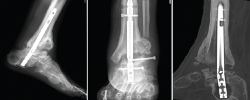

Figura 6. Imagen radiográfica y clínica en la que se aprecia la rotura parcial del clavo. Rescate con placa tibiotalar en proyección radiográfica en carga.

En este caso, la extracción fue sencilla: una vez retirados los tornillos de bloqueo, se realizó, con el sistema extractor del clavo, la extracción del mismo sin dificultad, ya que se trataba de una rotura incompleta. Realizamos un nuevo legrado de las superficies óseas, perforación de las mismas, nuevo aporte de injerto de cresta ilíaca y fijación con placa de artrodesis tibiotalar (Palex Medical), ya que la articulación subtalar estaba consolidada (Figura 6).